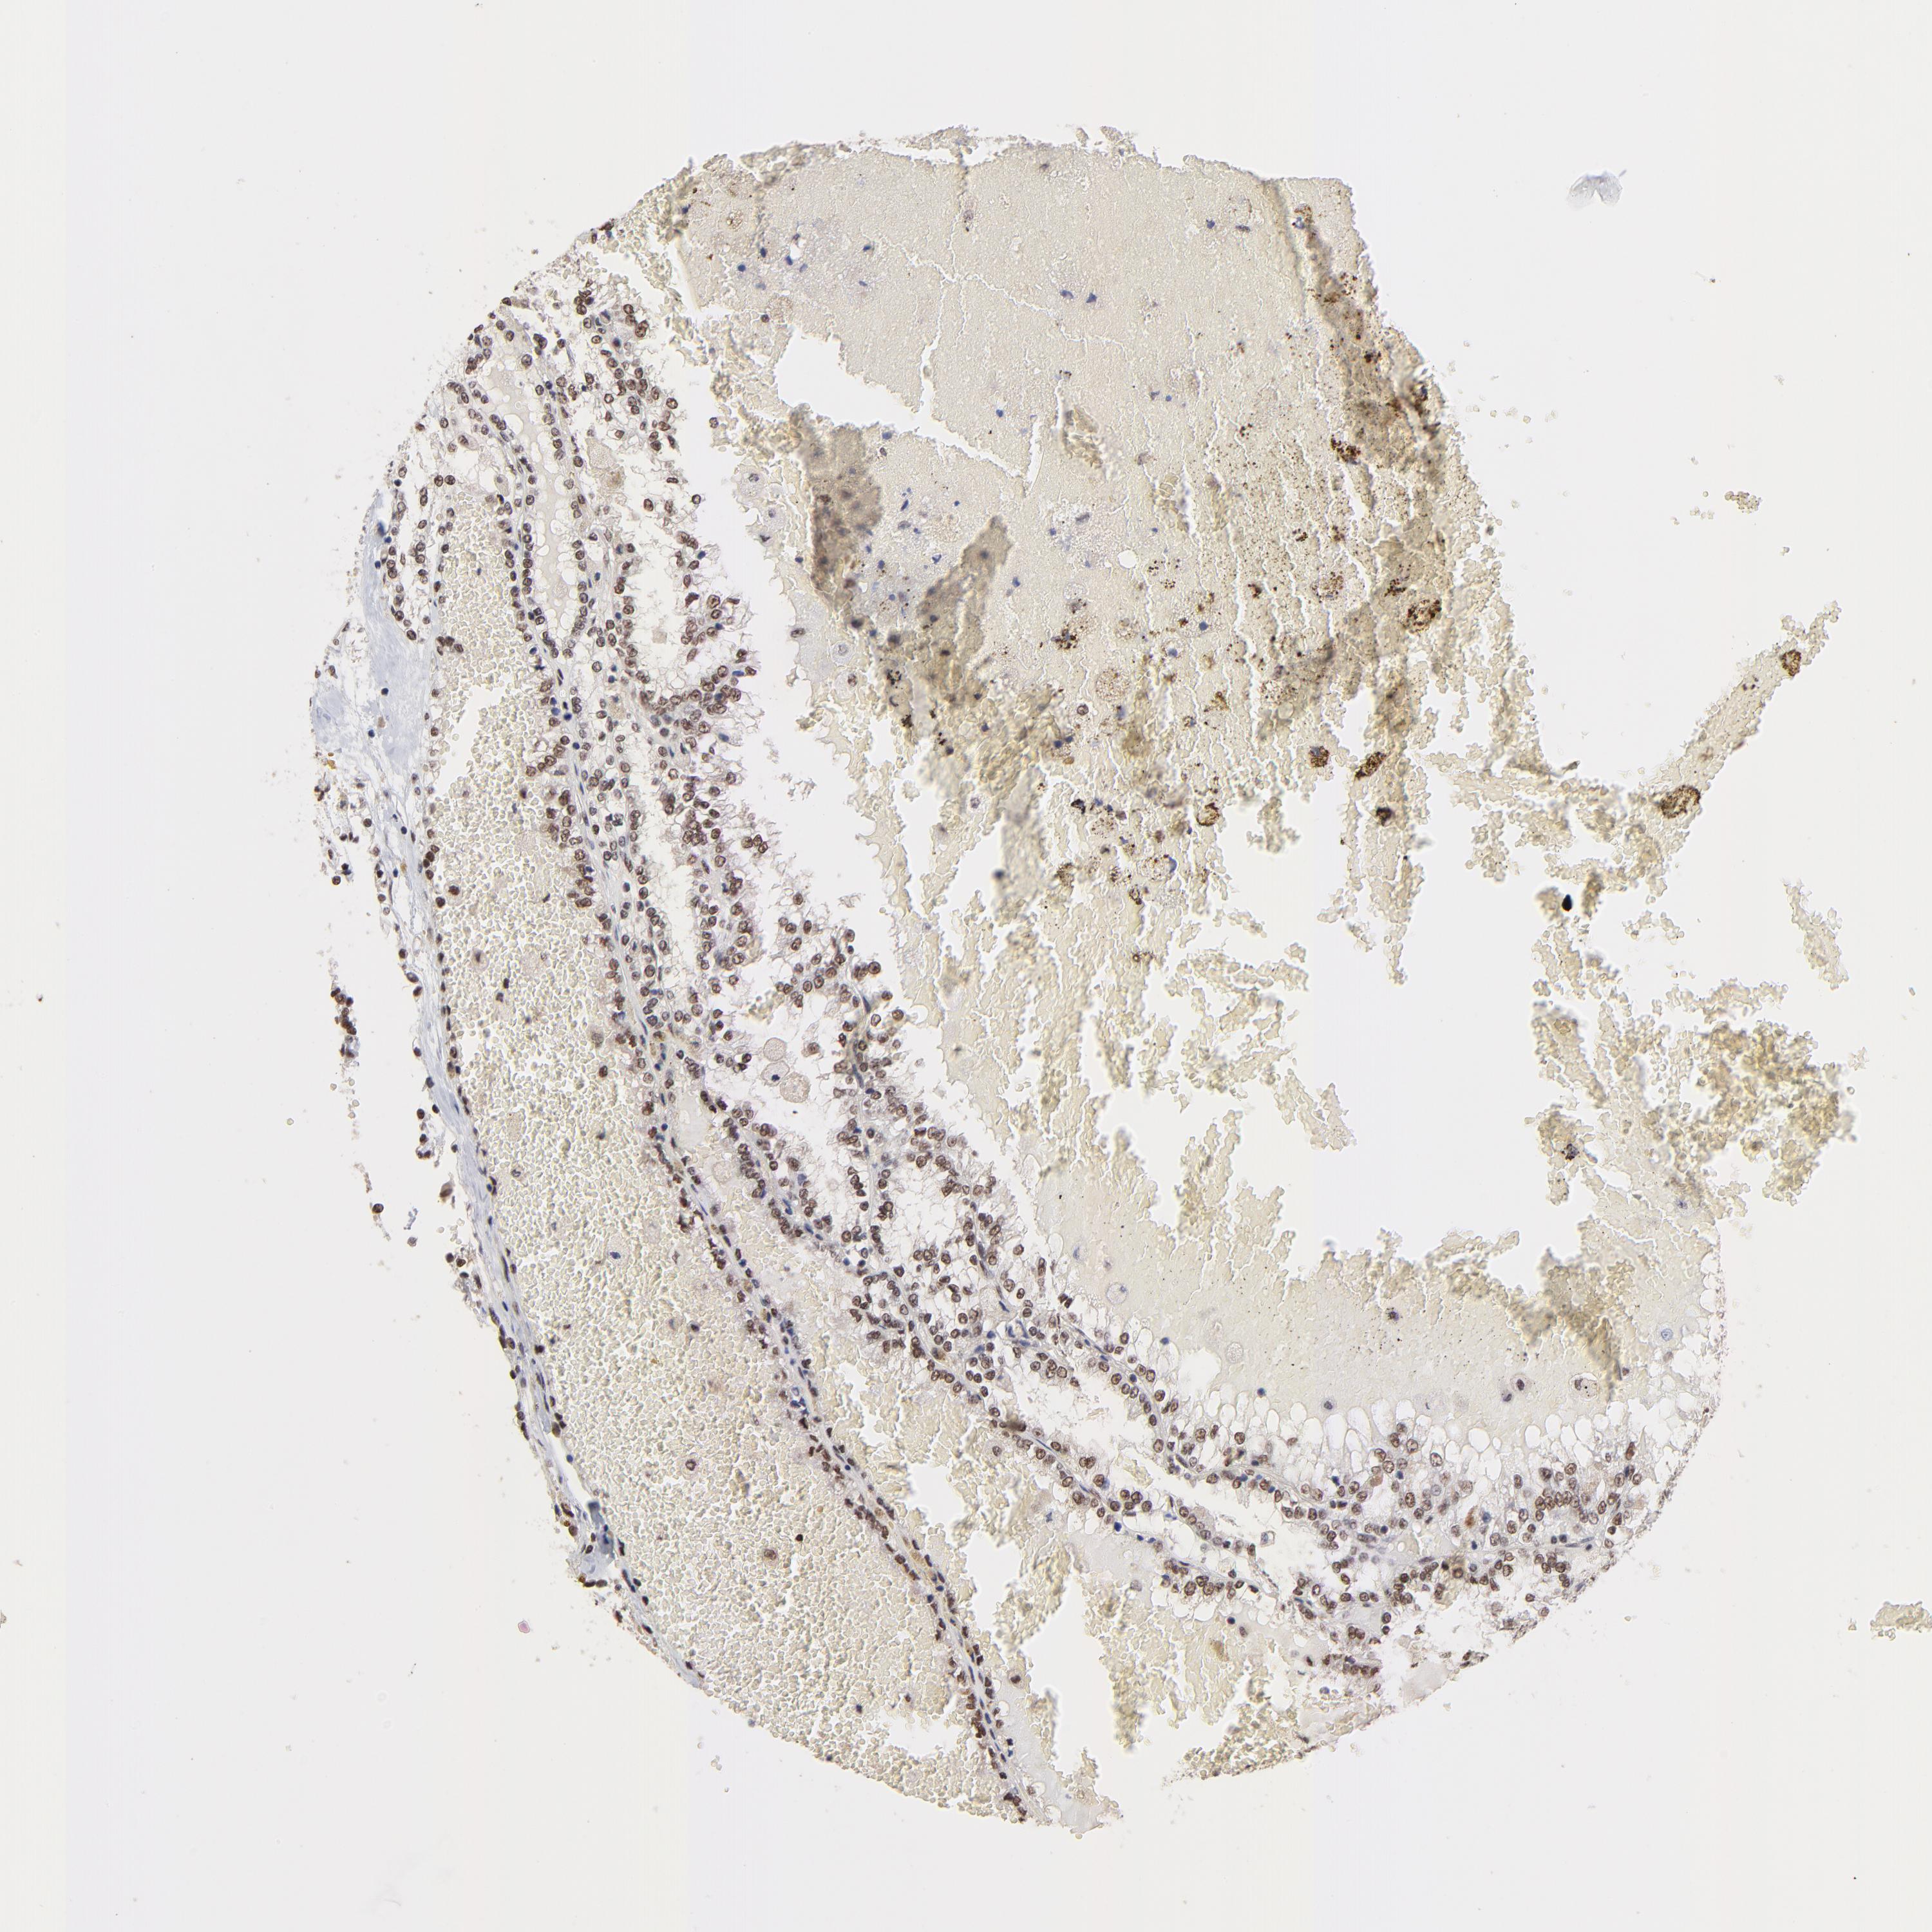

KIDNEY RENAL CLEAR CELL CARCINOMA (VALIDATION) - Interactive survival scatter ploti

The Survival Scatter plot shows the clinical status (i.e. dead or alive) for all individuals in the patient cohort, based on the same data that underlies the corresponding Kaplan-Meier plots. Patients that are alive at last time for follow-up are shown in blue and patients who have died during the study are shown in red.

The x-axis shows the expression levels (FPKM) of the investigated gene in the tumor tissue at the time of diagnosis. The y-axis shows the follow-up time after diagnosis (years). Both axes are complimented with kernel density curves demonstrating the data density over the axes. The top density plot shows the expression levels (FPKM) distribution among dead (red) and alive patients (blue). The right density plot shows the data density of the survived years of dead patients with high and low expression levels respectively, stratified using the cutoff indicated by the vertical dashed line through the Survival Scatter plot. This cutoff is automatically defined based on the FPKM cutoff that minimizes the p-score. The cutoff can be changed by dragging the vertical line or by entering a cutoff value in the square labeled "Current cut-off".

Under the Survival Scatter plot the p-score landscape (black curve; left axis) is shown together with dead median separation (red curve; right axis). Dead median separation is the difference in median mRNA expression between patients who have died with high and low expression, respectively. It is calculated as follows: median FPKM expression of dead patients with high expression - median FPKM expression of dead patients with low expression. This is intended to aid the user in visually exploring custom cutoffs and the associated p-scores and dead median separation.

Individual patient data is displayed and can be filtered by clicking on one or more of the category buttons on the top of the page. Categories describing expression level and patient information include: high, low, alive, dead, female, male and tumor stages. The scale of the x-axis can be toggled between linear and log-scale by clicking on the "x log" button. Mouse-over function shows TCGA ID, patient information and mRNA expression (FPKM) for each patient.

& Survival analysisi

Kaplan-Meier plots summarize results from analysis of correlation between mRNA expression level and patient survival. Patients were divided based on level of expression into one of the two groups "low" (under cut off) or "high" (over cut off). X-axis shows time for survival (years) and y-axis shows the probability of survival, where 1.0 corresponds to 100 percent.

DSN1 is not prognostic in Kidney Renal Clear Cell Carcinoma (validation)

Best expression cut offi

Based on the FPKM value of each gene, patients were classified into two groups and association between prognosis (survival) and gene expression (FPKM) was examined. The best expression cut-off refers the FPKM value that yields maximal difference with regard to survival between the two groups at the lowest log-rank P-value. Best expression cut-off was selected based on survival analysis .

When clicking on this number, the vertical dashed line indicating cut-off, the interactive survival plot, and the Kaplan-Meier curve will be adjusted to show results based on the best expression cut-off.

: 10.68

P scorei

Log-rank P value for Kaplan-Meier plot showing results from analysis of correlation between mRNA expression level and patient survival.

N/A

Average pTPM 11.2

Number of samples 100